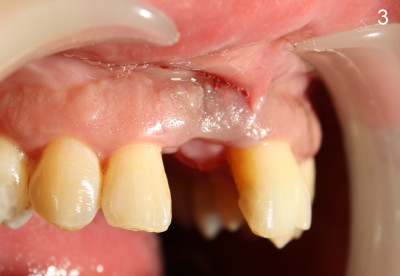

The upper right central incisor is nonsalvageable for 37-year-old man (Fig.1).  After atraumatic extraction, localized scaling is performed.  Collagen plug is inserted.  PGA suture is used to keep the plug in place.

The patient is scheduled to return 1 week later for #8 socket debridement and irrigation.  The labial aspect has undergone atrophic changes (Fig.3,4).  More surprisingly is that the labial plate is found to be lost during socket debridement.  The labial plate seems to be intact at extraction.  Otherwise socket preservation must have been done.

Does this post-extraction infection happens often, but without being noticed?  Four quadrant scaling and root planing should have been conducted prior to extraction to reduce infection in this case. Note calculus in the lower anteriors (Fig.1).   Does immediate implant with bone graft prevent loss of the labial plate?   What should we do for this case now?  Wait for 2-3 months before implant placement?  Or bone graft after the infection is under control?